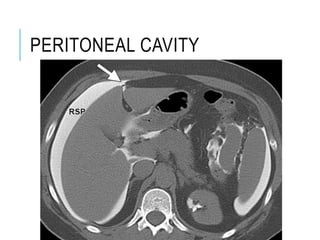

PERITONEAL CAVITY